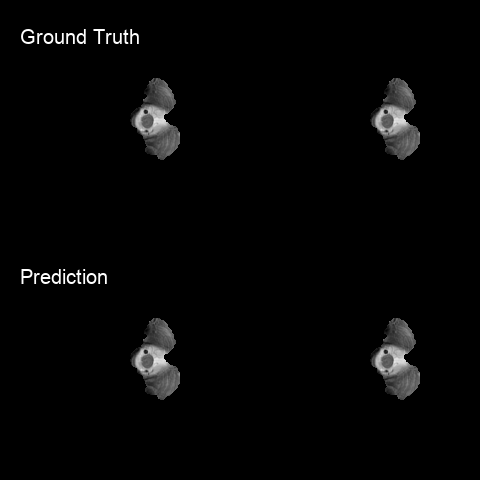

I designed a deep-learning-based approach based on U-Net for automatic brain glioma segmentation of multimodal MRI scans with high efficiency and accuracy and achieved the 4th place in the 2018 Multimodal Brain Tumor Segmentation Challenge.